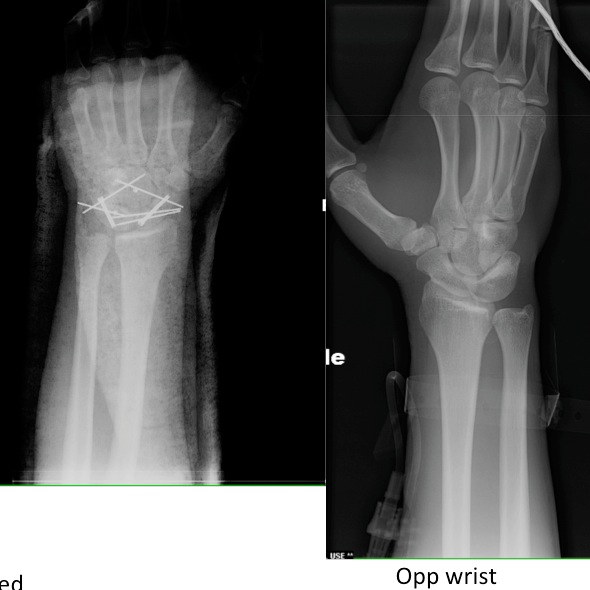

Courtesy